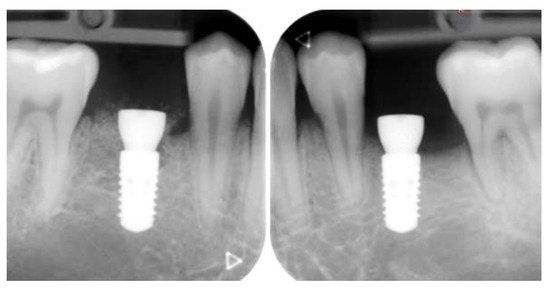

2.4.1. Radiographic Measurements

3.2. Marginal Bone Level Outcomes

| Mesial Marginal Bone Level (2D) [mm] after Immediate Placement | ||||||||

|---|---|---|---|---|---|---|---|---|

| Patient | 1 | 2 | 3 | 4 | 5 | Median | IQR | |

| Implant position | 45 | 35 | 45 | 45 | 13 | 23 | NA | NA |

| Post-OP mesial | 1.8 | 0.0 | 0.1 | 3.0 | 0.4 | 0.4 | 0.4 | 0.18–1.45 |

| 1 year mesial | 0.6 | 0.0 | 0.1 | 1.5 | 0.1 | 0.1 | 0.1 | 0.1–0.48 |

| Post-OP distal | 1.2 | 0.0 | 0.1 | 3.0 | 0.4 | 0.4 | 0.4 | 0.18–1.0 |

| 1 year distal | 0.6 | 0.0 | 0.1 | 1.5 | 0.2 | 0.0 | 0.2 | 0.03–0.5 |

| Marginal Bone Level (2D) [mm] after Delayed Placement | ||||||||

| Implant position | 35 | 45 | 35 | 35 | 35 | 45 | NA | NA |

| Post-OP mesial | 2.0 | 1.0 | 0.2 | 0.6 | 0.2 | 0.2 | 0.4 | 0.2–0.9 |

| 1 year mesial | 1.6 | 0.5 | 0.0 | 0.3 | 0.1 | 0.1 | 0.3 | 0.1–0.45 |

| Post-OP distal | 0.0 | 0.5 | 0.0 | 0.6 | 0.1 | 0.1 | 0.1 | 0.03–0.4 |

| 1 year distal | 0.0 | 0.2 | 0.0 | 0.3 | 0.1 | 0.1 | 0.1 | 0.03–0.18 |